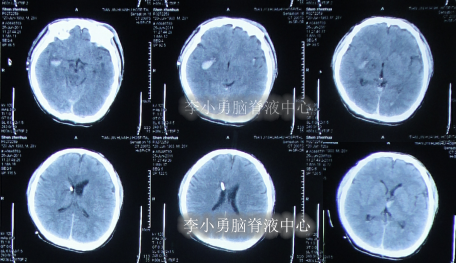

高压氧治疗15天即2011年8月19日,查头部CT示脑室周水肿,仍有颅内出血(图-9)。

图-9:2011年8月19日头部CT

图-10:2011年9月14日头部CT

2012年9月11日,入院时:神志模糊,反应迟缓。头颅额部右侧手术瘢痕,双眼睑轻度浮肿,左眼眶凹陷,两侧瞳孔对光反射右侧存在,左侧消失,大小便失禁,体温高达39.5°C,发病以来体型消瘦,不能遵嘱活动,刺痛后四肢有反应但无发声,不能言语,饮食差,四肢肌张力增高,左上肢肌屈曲强直,余肢体肢活动受限,肌力3级(图-13),头部CT示脑干弥漫性皱缩损伤后,脑积水(图-14)。

图-14:2012年9月11日头部CT

脑室外引流术后12天即2012年9月24日,患者体温连续1周正常,意识模糊好转为了嗜睡。查头部CT示脑室外引流术状态(图-15)。

图-15:2012年9月24日头部CT